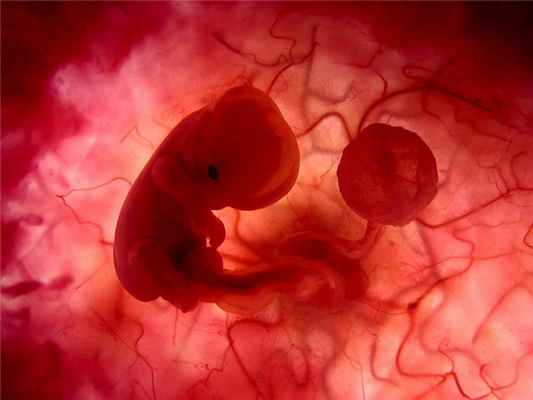

- фетальный (срок до 4 недель включительно);

- эмбриональный (срок 5-9 недель включительно);

- фетальный (срок 10-21 неделя).

По сроку беременности выкидыши классифицируют на ранние (до 9-й недели беременности) и поздние (с 10-й по 21-ю недели беременности). Классификация по стадии развития плодного яйца выделяет преэмбриональный (до 4-й недели беременности), эмбриональный (с 5-й по 9-ю недели) и фетальный (с 10-й по 21-ю недели) выкидыш.